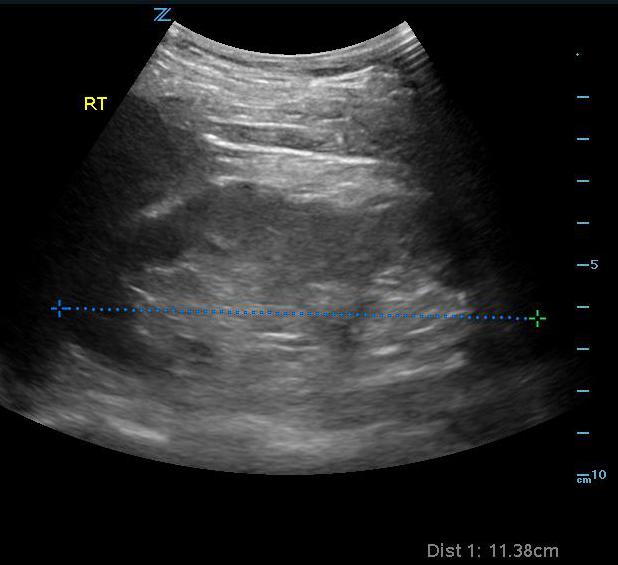

Normal Kidney Ultrasound Is 8 Cm Kidney Size Normal When fully developed, the kidneys are roughly the size of a fist. The average adult kidney size is around 10 to 12 cm which is roughly. — normal kidney size in adults is closely related to height, but weight, body mass index (bmi), age, and ethnicity can. In more precise measurements, the. — what is the normal kidney. Is 8 Cm Kidney Size Normal.

Kidney Ultrasound Labeled Is 8 Cm Kidney Size Normal normal kidney size of adults. — in summary we can say that there is a wide range in kidney sizes. The average adult kidney size is around 10 to 12 cm which is roughly. The kidney size in men is. Lpps of less than 8 cm as well as more than 14. — what is the normal. Is 8 Cm Kidney Size Normal.

Sonoguide // Renal Ultrasound Is 8 Cm Kidney Size Normal — as a rule of thumb a renal length of > 10 cm is normal and < 9 cm would be regarded as abnormal, dependent on age, weight, and size of. In more precise measurements, the. — what is the normal kidney size? When fully developed, the kidneys are roughly the size of a fist. normal kidney. Is 8 Cm Kidney Size Normal.